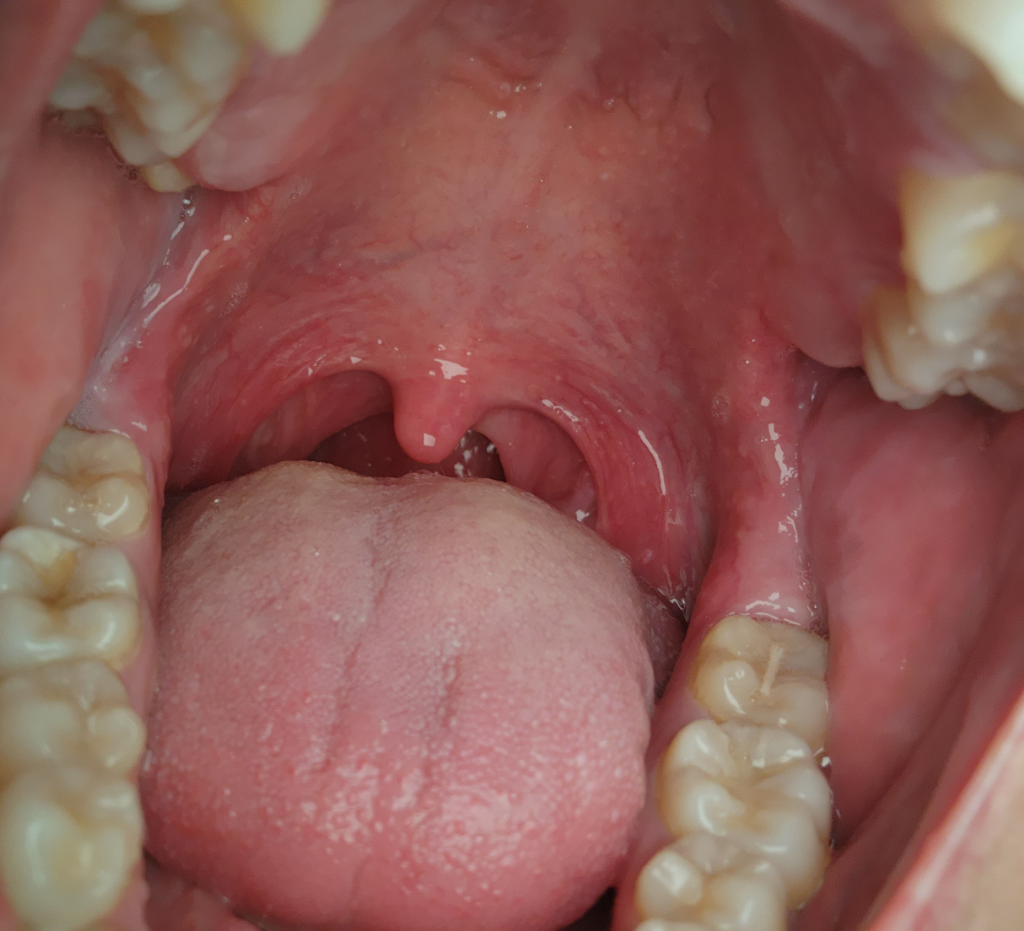

구후융기 쪽이 부은 것 같습니다

이틀전부터 음식을 씹을 때마다 잇몸이 같이 씹히는

불편감이 있었는데 후레쉬로 밝혀서 보니 동그라미 친

부분이 반대쪽과 비교해봤을때 빨갛게 부은 것 같습니다

자연치유가 될 수 있을까요?

• 1번 째 사진